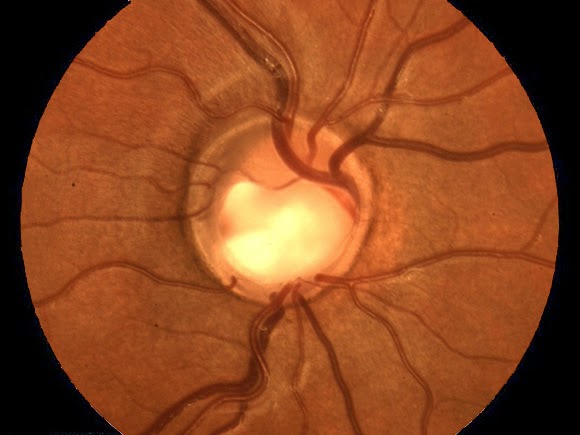

ΠερισσότεραΠαγκόσμια Εβδομάδα Γλαυκώματος: Μάθετε για το γλαύκωμα και προστατεύστε τα μάτια σας πριν να είναι πολύ αργά

Ο AΘΟΡΥΒΟΣ ΚΛΕΦΤΗΣ ΤΗΣ ΟΡΑΣΗΣ Παγκόσμια Εβδομάδα Γλαυκώματος: Μάθετε για το γλαύκωμα και προστατεύστε τα μάτια σας πριν να είναι πολύ αργά 67 εκατομμύρια άνθρωποι σε όλο τον κόσμο πάσχουν από γλαύκωμα Το γλαύκωμα συνήθως δεν εμφανίζει συμπτώματα και μπορεί να παραμείνει επί μακρόν αδιάγνωστο. Oι ασθενείς πριν καν αντιληφθούν …

ΠερισσότεραΤο γλαύκωμα είναι η δεύτερη πιο κοινή αιτία τύφλωσης

Περισσότεροι από 6,7 εκατομμύρια άνθρωποι θα τυφλωθούν από γλαύκωμα παγκοσμίως τα επόμενα πέντε χρόνια (2020), σύμφωνα με εκτίμηση του Παγκόσμιου Οργανισμού Γλαυκώματος! Η δυσοίωνη αυτή εκτίμηση οφείλεται στο γεγονός ότι το γλαύκωμα είναι η δεύτερη πιο κοινή αιτία τύφλωσης παγκοσμίως καθώς στα αρχικά στάδια δεν προκαλεί συμπτώματα και όταν διαγνωστεί …